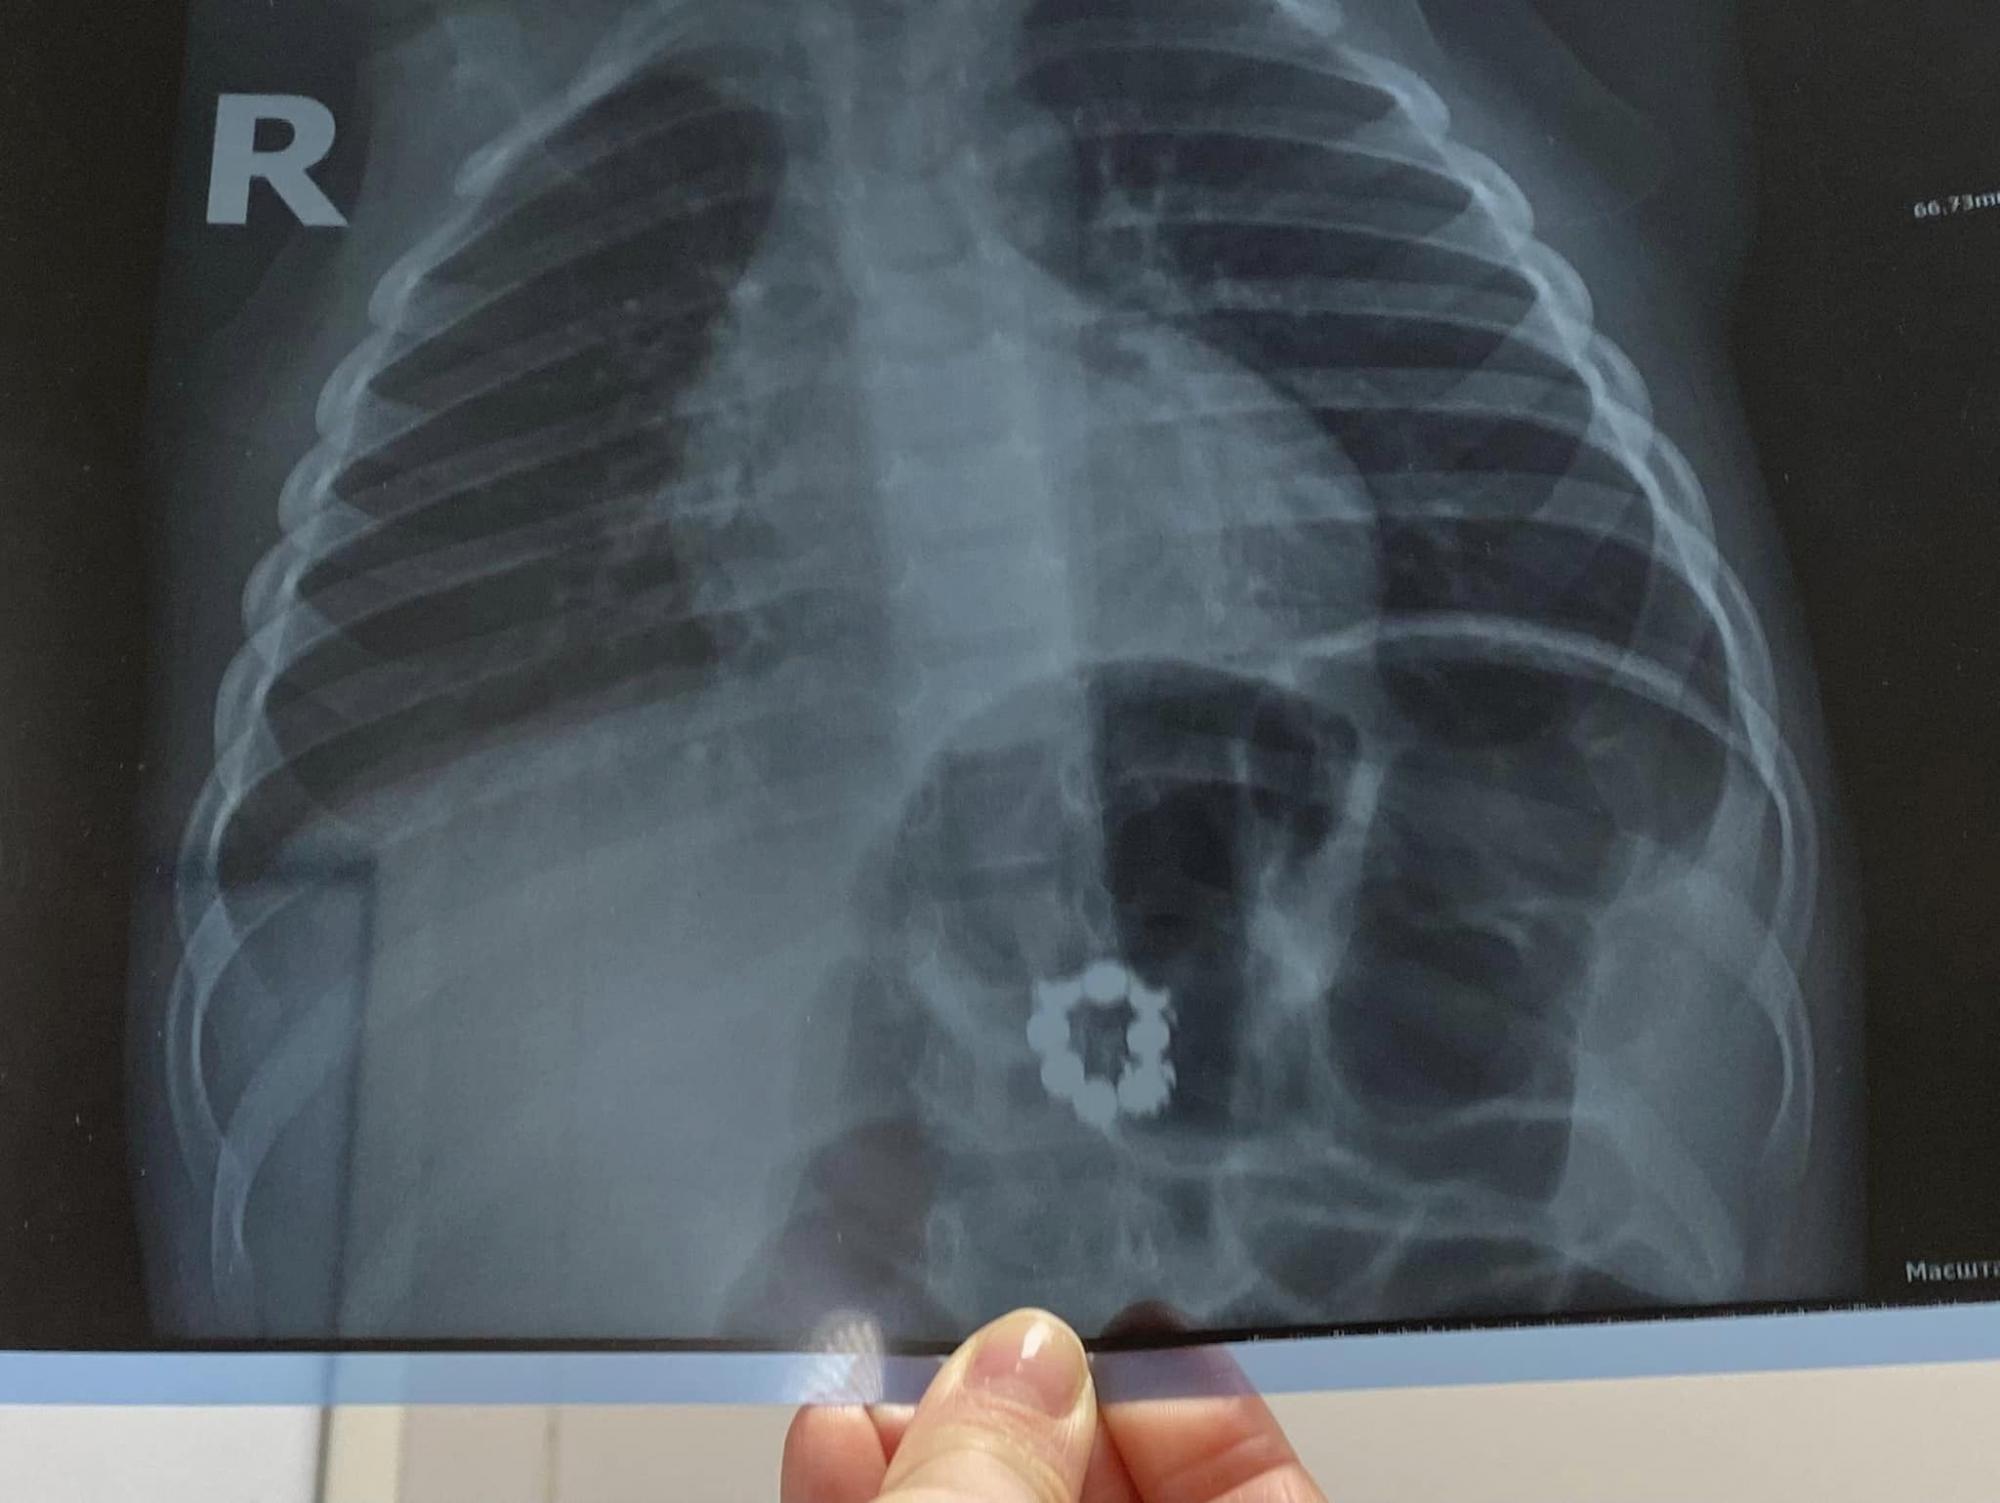

Дело в том, что магниты у ребенка обнаружили случайно - родители мальчика обратились к врачу, когда сынишка простудился. И во время обследования маленького пациента у педиатра медик назначил рентген-снимок, на котором с удивлением увидели... 8 магнитов, замкнутых в круг.

Магниты в теле трехлетнего мальчика обнаружили на рентгеновском снимке (фото: facebook.com/ndslohmatdyt)